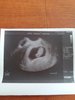

Dziewczynki wszystko ok. Fajny ten lekarz z nfz. Badania mi wszystkie przepisal, zrobil wymaz, zbadal full wersion ;) i poswiecil mi chyba z 45 min. Potraficie z tego zdjecia odczytac wielkosc dzidzi, bo z nerwow zapomnialam zapytac... Przez te nerwy mialam ciśnienie wyższe i kazal badac 3 razy dziennie i zapisywac wyniki...

Super :) ja nie widze tu crl wogole.